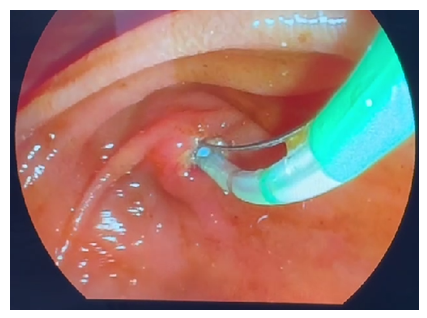

During the second stage of surgery (Rendezvous), joint work of surgical and endoscopic teams is necessary. The surgeon performed an incision of the cystic duct just below the previously applied clip and inserted a 0.035 Fr endoscopic string 450 cm long into the cystic duct through a 3 mm diameter trocar. Then he conducted it antegradely through the LDP into the lumen of the duodenum. After the string was passed through the LDP, the endoscopist conducted a video duodenoscope in the duodenum in the usual way and visualized the LDP in the lumen of which the string was located. From the side of the lumen of the duodenum, the string was captured with a modified hollow endoscopic bougie (Fig. 3).At the third endoscopic stage of the hybrid surgical intervention, the papillot was lowered along the string and inserted into an ampoule of LDP, thus performing selective intubation of the choledochus. Retrograde endoscopic papillosphincterotomy (EPST) was performed using the standard method (Fig. 4).Then the papilloma was removed, leaving an endoscopic string in the biliary tract. Depending on the diameter of the common bile duct and the size of the stones, lithoextraction was performed with four-string Dormia baskets of various sizes and stiffness (Fig. 5).  | Figure 3. Capturing the string in the lumen of the duodenum |

| Figure 5. Choledocholithoextraction |